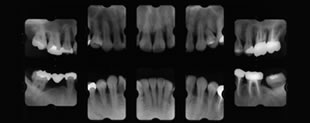

レントゲン検査 |

肉眼で見えない歯を支える骨を調べる |